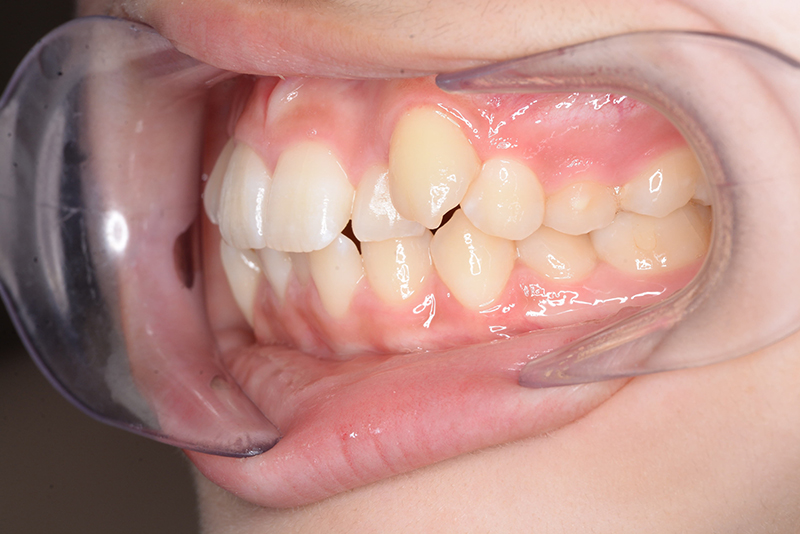

| 口腔内所見 | over jet 3.8mm、over bite 30mm、臼歯関係I級、上下顎前歯部に叢生が認められ、下顎正中は右側へ4.5mm偏位していた。左上5はCRの治療痕が認められた。 |

| 批評・予后 | 治療後において閉唇時の頤筋の過緊張の改善及び咬合の緊密化と歯根のパラレリングが認められ、良好な咬合が確立できたと思う。 現在は保定をしつつ下顎両側第三大臼歯抜歯の抜歯を検討している。 |